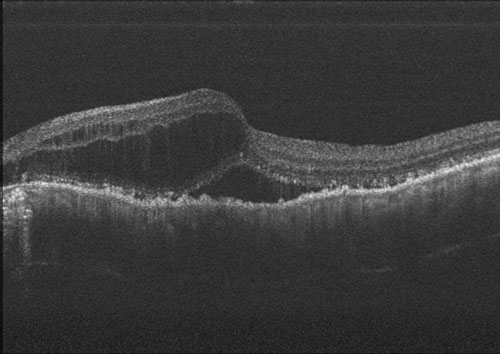

加齢黄斑変性